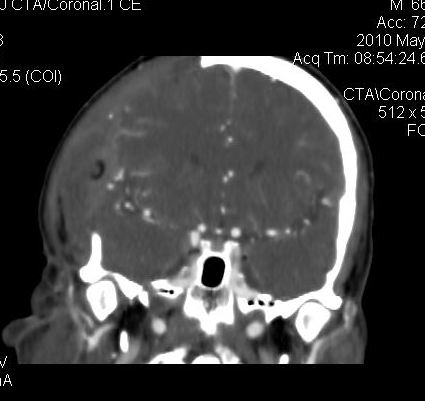

男.60岁,渐进性意识不清,ct检查双侧额颞顶部硬膜下血肿,开颅术后行脑血管cta,大脑中动脉起始部见一瘤状血管扩张。请各位老师留下宝贵意见

太常见了,报动脉瘤就可以

符合动脉瘤表现。

符合动脉瘤表现。

动脉瘤。

颅内动脉瘤。

后重建做得不是很好看,要将维蒂斯环充分显示,最好在增加一个mip。这样不好定位。

小动脉瘤

典型

符合动脉瘤的表现

动脉瘤

符合动脉瘤表现。

小动脉瘤

典型